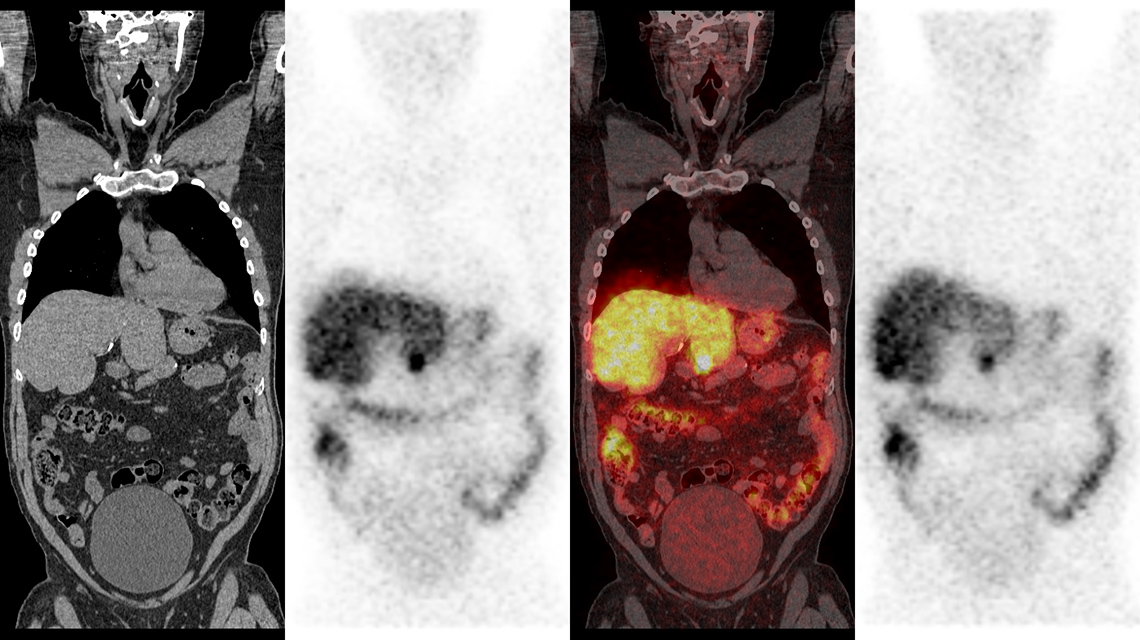

The Atlas is presented in three main sections, firstly reviewing the usage of CT and SPECT images and the various systems currently available. Secondly, the quality control procedures for the operation of SPECT and SPECT/CT systems in routine clinical practice are outlined. The concluding section presents a broad selection of 39 well-illustrated case studies of potential image artefacts from different sources, ranging from hardware malfunctions to user- and patient-induced artefacts. In addition, descriptions are given of their causes and the techniques used to identify them and avoid their recurrence.

“A useful and reliable diagnosis from SPECT/CT imaging depends on the accurate interpretation of the images,” said Ms. van der Merwe. “Possible image abnormalities related to machine, user or patient factors might not be recognized by nuclear medicine professionals, which could ultimately hinder optimal patient management.” She continued, “the case studies illustrated in the SPECT/CT Atlas will help practitioners identify and eliminate these abnormalities.”